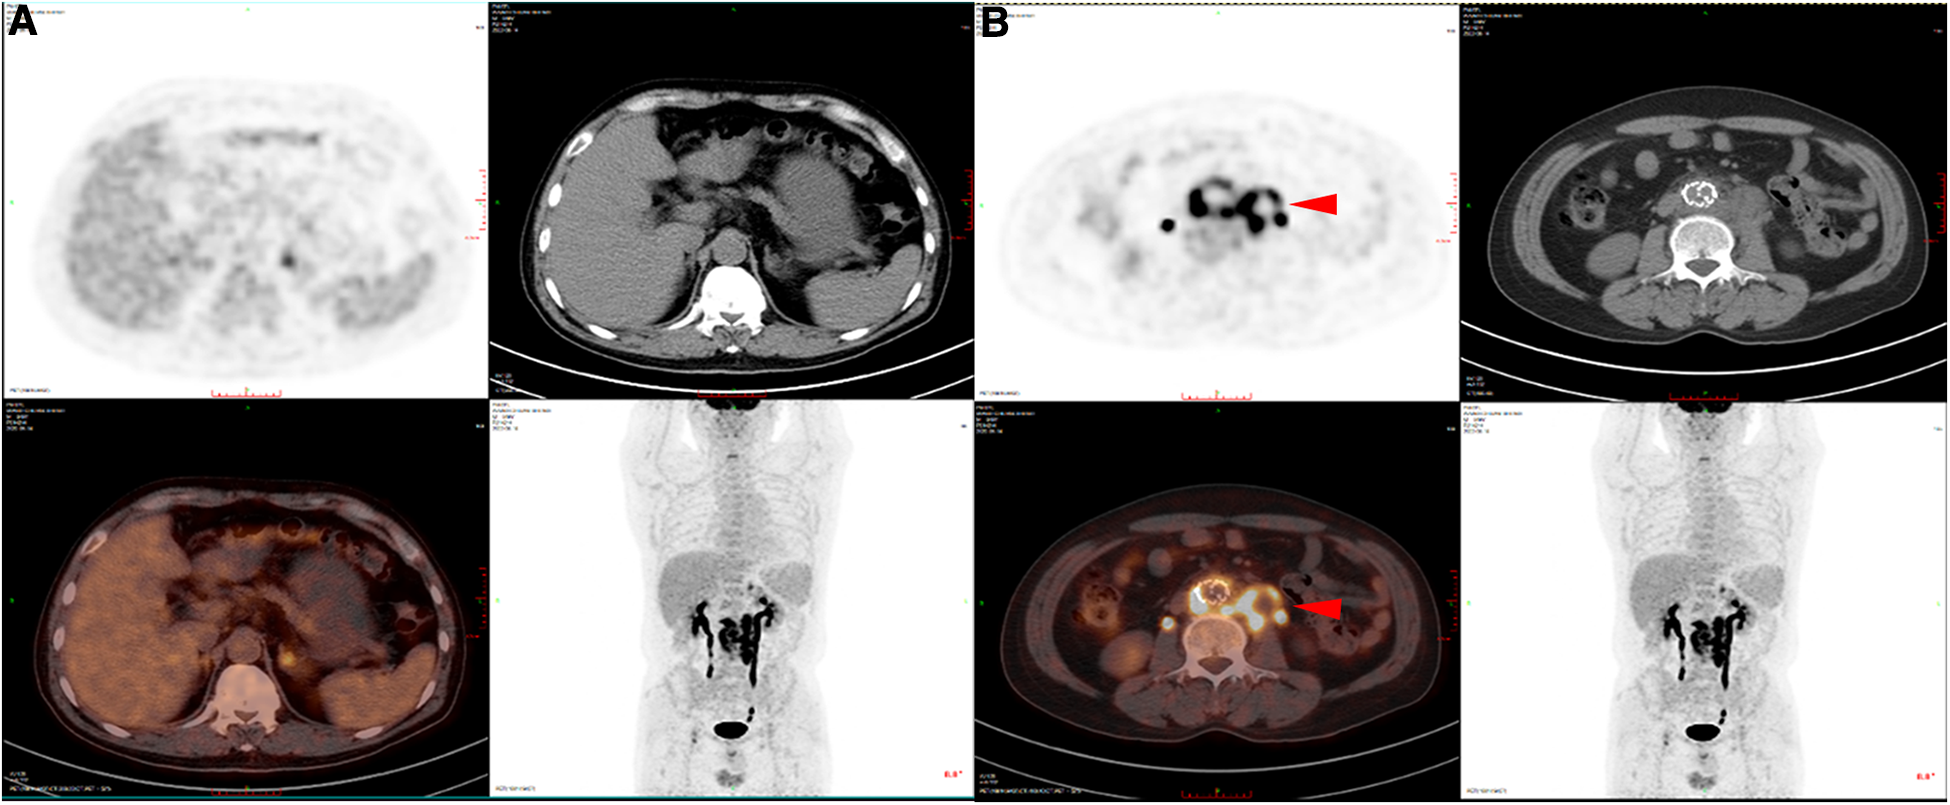

This retrospective study was approved by the Ethics Committee of Nanjing Drum Tower Hospital (registration number: 2017-015-05), and all patients provided consent for their participation. Between November 2021 and December 2022, patients with SGI were treated with removal of the infected grafts and surrounding infected tissues and revascularization (five men, one woman; mean age, 64 years; range, 49–79 years). Prior to identification of the specific infection and sensitive antibiotics, patients were treated with empiric broad-spectrum antibiotics, and surgical treatment was performed when the patient's clinical symptoms were relieved (abdominal pain, elevated body temperature and presence of inflammatory indicators). If the patient's condition worsened, emergency surgery was considered. All patients presented with postoperative fever or pain after EVAR (persistent fever in five patients and pain in the left lower abdomen in one patient). Currently, the diagnosis of SGI relies mainly on imaging, clinical presentation and laboratory indicators. The patients commonly presented with postoperative fever, and the imaging results typically showed an annular low-density shadow around the aorta, gas, and multiple floc shadows and lymph node shadows (with partial enlargement) (Figure 1A,B); the relevant inflammatory indicators (leukocytes, neutrophils, interleukin-6) were significantly increased. Aortic CT angiography (CTA) was commonly used, as was positron emission tomography/computed tomography (PET-CT). For some more insidious lesions, PET-CT has obvious advantages. PET-CT perfectly integrates PET and CT. PET provides detailed functional and metabolic molecular information of the lesion, while CT provides precise anatomical location of the lesion. Thus, PET-CT can achieve early detection of lesions and diagnosis of diseases (the radionuclide we used was 18F-FDG) (Figure 2A,B). Fever was defined as an axillary temperature above 38.0°C. The patient characteristics are summarized in the Table.

Figure 2

PET-CT of SGI patients. (A) PET-CT images of non-infected sites showed no obvious fluorescence enhancement. (B) PET-CT images of the infected sites showed obvious fluorescence enhancement.